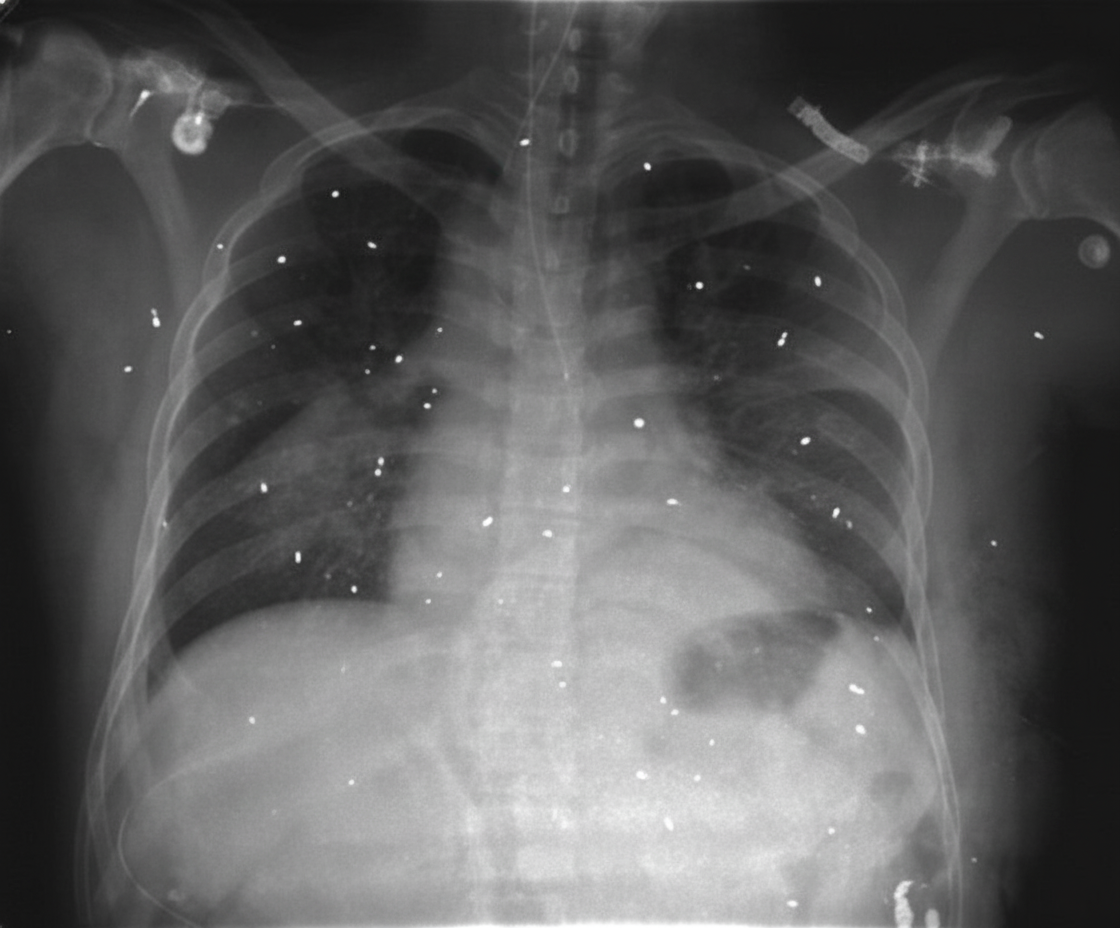

A 29-year-old man with a history of substance abuse presented with headache, fever, and metallic taste in his mouth. His physical exam was normal except for needle tracks in his right arm. A chest X-ray was performed. Based on the chest X-ray findings, what is the most likely diagnosis?

Explanation: ***Pulmonary embolization of metallic particles*** - **IV drug abuse** with **needle tracks** and **metallic taste** indicates injection of crushed oral medications containing **metallic excipients** (talc, magnesium stearate) that embolize to pulmonary vessels. - Chest X-ray typically shows **bilateral lower lobe opacities** with **reticulonodular pattern** from foreign body deposition in pulmonary capillaries. *Primary tuberculosis* - Would present with **unilateral upper lobe consolidation** or **hilar lymphadenopathy** on chest X-ray, not the bilateral pattern expected in metallic particle embolization. - **Metallic taste** is not a typical symptom of tuberculosis; patients usually present with **night sweats**, **weight loss**, and **chronic cough**. *Silicosis* - Requires **occupational exposure** to silica dust (mining, sandblasting) over years, not acute presentation in a young substance user. - Chest X-ray shows **upper lobe fibrosis** and **eggshell calcification** of hilar lymph nodes, different from acute bilateral opacities. *Sarcoidosis* - Typically presents with **bilateral hilar lymphadenopathy** and **upper lobe reticulonodular opacities** on chest X-ray. - **Metallic taste** and **needle tracks** are not associated with sarcoidosis; patients usually have **dry cough** and **shortness of breath**.